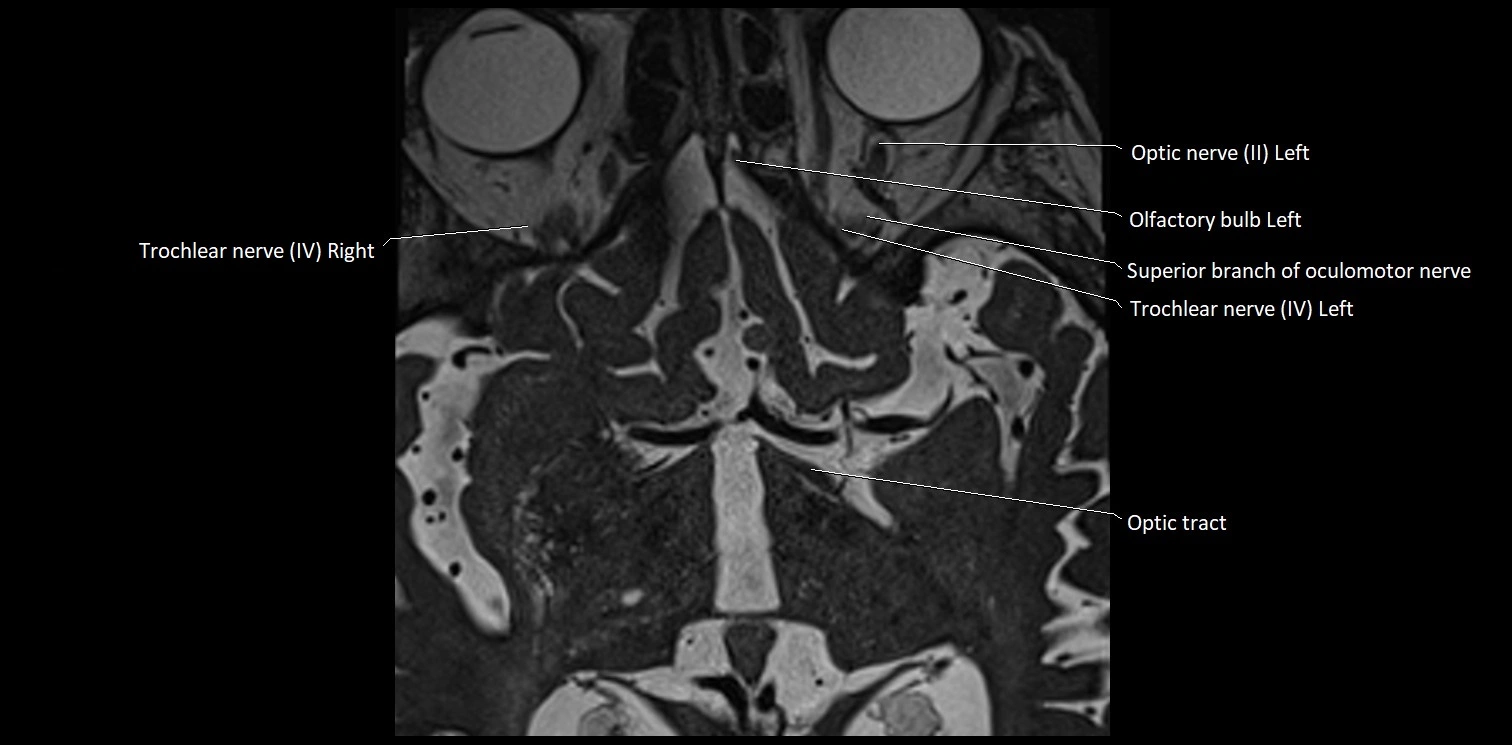

MRI Appearance

• The abducens nerve is a small, thin, linear structure

• Best visualized on high-resolution T2-weighted 3D MRI sequences (e.g., FIESTA or CISS)

• Seen as a hypointense (dark) line running from the brainstem at the pontomedullary junction, traversing the prepontine cistern, and entering Dorello’s canal under the petrosphenoidal ligament, then into the cavernous sinus, and finally the orbit

• May be challenging to visualize in standard MRI due to its small size

• Pathology may be inferred by absence, displacement, or enhancement of the nerve